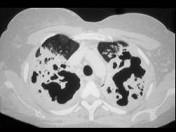

问题 一养鸽女,48岁,发热,咳嗽,咳浓痰带血半月余,请结合CT,选出最可能的诊断 ( )

选项 A.原发性肺结核 B.肺曲菌病 C.肺癌 D.间质性肺炎 E.支气管扩张

答案 B